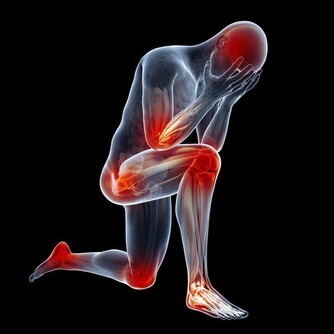

5、走路時有絞痛感當走路或移動時,你的臀部和腿部肌肉有痙攣和絞痛感,稍作休息後有所改善,

可不要以為只是年紀大了或缺乏鍛煉所致,要警惕是外周動脈疾病的信號。

外周動脈疾病,也被稱為PAD。

如果你走路時出現絞痛感,很可能是患了PAD,那麼你的心臟動脈有一半被堵塞的風險。

但也不要太恐慌,PAD是可以治癒的。